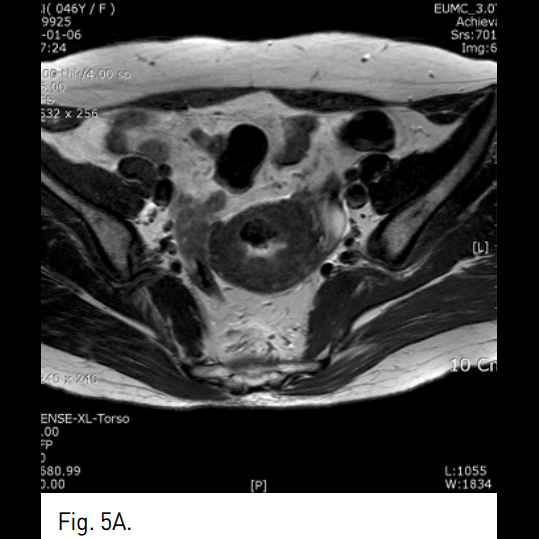

Fig. 5

A-C. One year follow-up T2-weighted transverse (A), coronal (B), sagittal (C) MR images show a small remnant of myoma with low signal intensity.